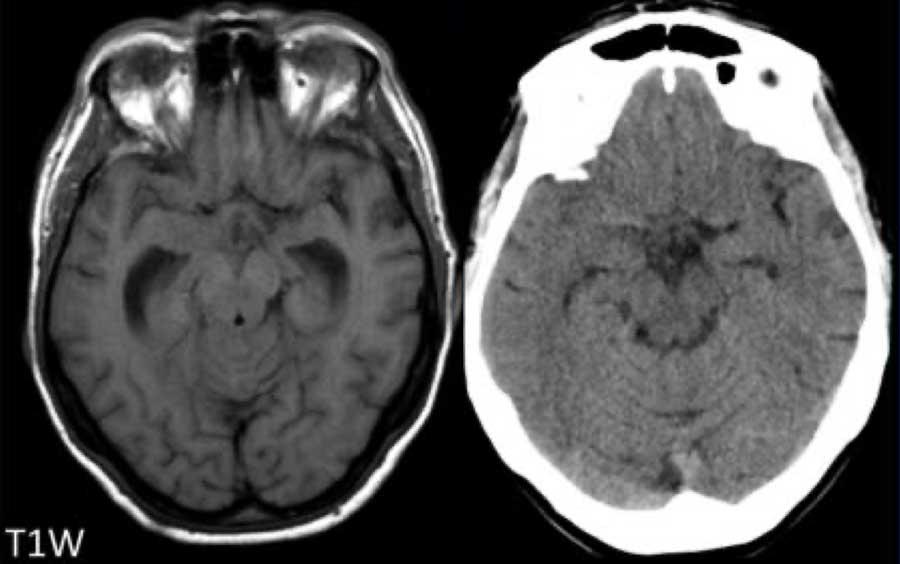

Bệnh nhân này nhập viện với hình ảnh khối máu tụ tiểu não.

Tiếp tục xem hình ảnh chuỗi xung T1W…

Chuỗi xung T1W cho thấy ổ xuất huyết tăng tín hiệu (mũi tên).

Xuất huyết nội sọ do tăng huyết áp cùng với CAA chiếm 80% nguyên nhân gây khối máu tụ trong nhu mô não.

Cần nghĩ đến CAA khi phát hiện nhiều ổ xuất huyết ngoại vi hoặc xuất huyết thùy ở bệnh nhân cao tuổi.